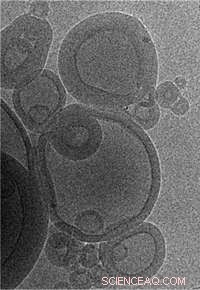

MIT engineers created vaccine-delivering nanoparticles by placing lipid spheres inside one another. Credit: Peter DeMuth and James Moon

Irvine, who is a member of MIT’s David H. Koch Institute for Integrative Cancer Research, decided to build on the liposome approach by packaging many of the droplets together in concentric spheres. Once the liposomes are fused together, adjacent liposome walls are chemically “stapled” to each other, making the structure more stable and less likely to break down too quickly following injection. However, once the nanoparticles are absorbed by a cell, they degrade quickly, releasing the vaccine and provoking a T cell response.